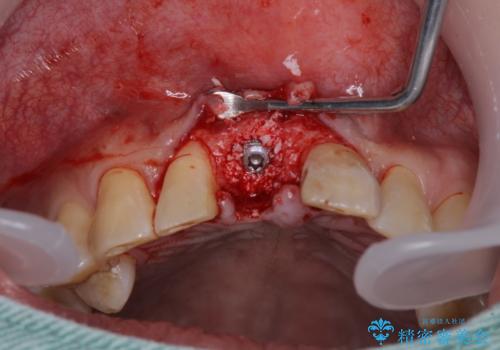

- 前歯の被せものが脱離したとのことで来院された患者様です。

診察の結果、前歯が縦に破折しており、抜歯が必要と診断されました。

補綴治療としては、インプラントあるいはブリッジの2つがありますが、患者様と相談した結果、インプラントによる補綴治療を選択することとなりました。